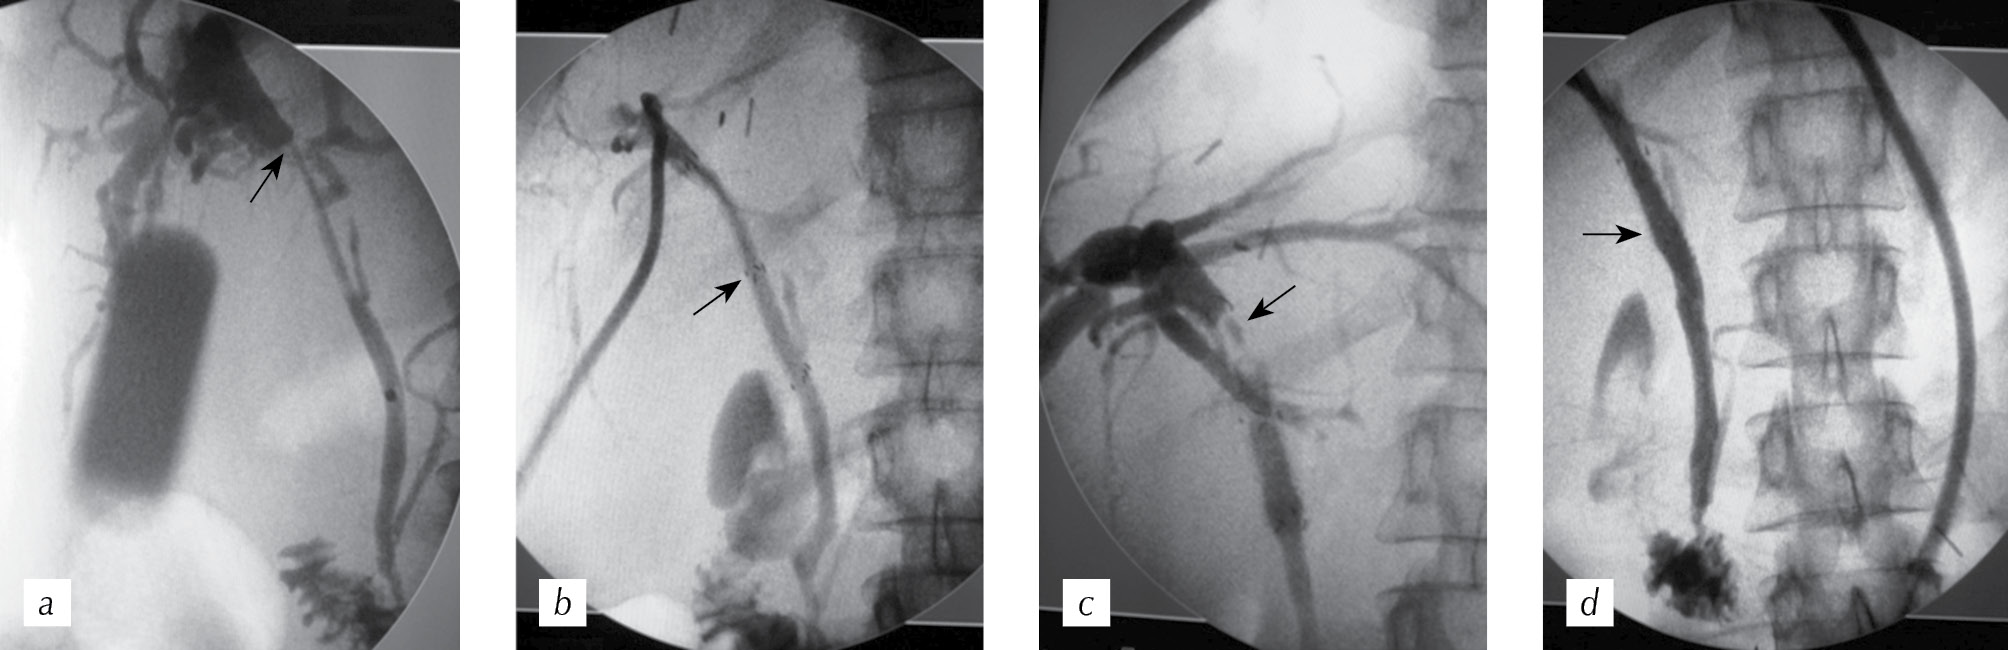

Given the possibility of preliminary positioning of the stent after trial opening, we formed perforations in the stent lining in the zone of interest. After that, it was finally installed (Fig. 2).

Fig. 2. Cholangiogram of the patient with primary sclerosing cholangitis (the arrows indicate the main pancreative duct and functioning gall bladder) (a); cholangiogram after stenting (the black arrows indicate the stents, the white arrows — the areas of artificially perforated holes) (b)

Рис. 2. Холангиограмма пациента с первичным склерозирующим холангитом (стрелками отмечены главный панкреатический проток и функционирующий желчный пузырь) (a); холангиограмма после стентирования (черными стрелками обозначены установленные стенты, белыми — зоны искусственно сформированных перфорационных отверстий) (b)

Fig. 2 presents the case of successful treatment of patient D., 34 years old, with primary sclerosing cholangitis. The patient had anatomical features of a joint return of CBD and MPD and a functioning gall bladder. After the draining intervention and regression of jaundice, the second stage was stenting with three SNSs. All stents were coated with a lasso. After the stents were preliminary positioned and partially perforated, an endoscopic installation of a stent of the right lobular duct was performed, and a percutaneous installation of the stent of the CBD and the left lobular duct was performed. After six months, the CBD stent migrated, and after five months, a single attack of cholangitis was noted when the hepatoprotectors were canceled independently and was stopped conservatively with antibiotics. The total follow-up period at present is 2.5 years.